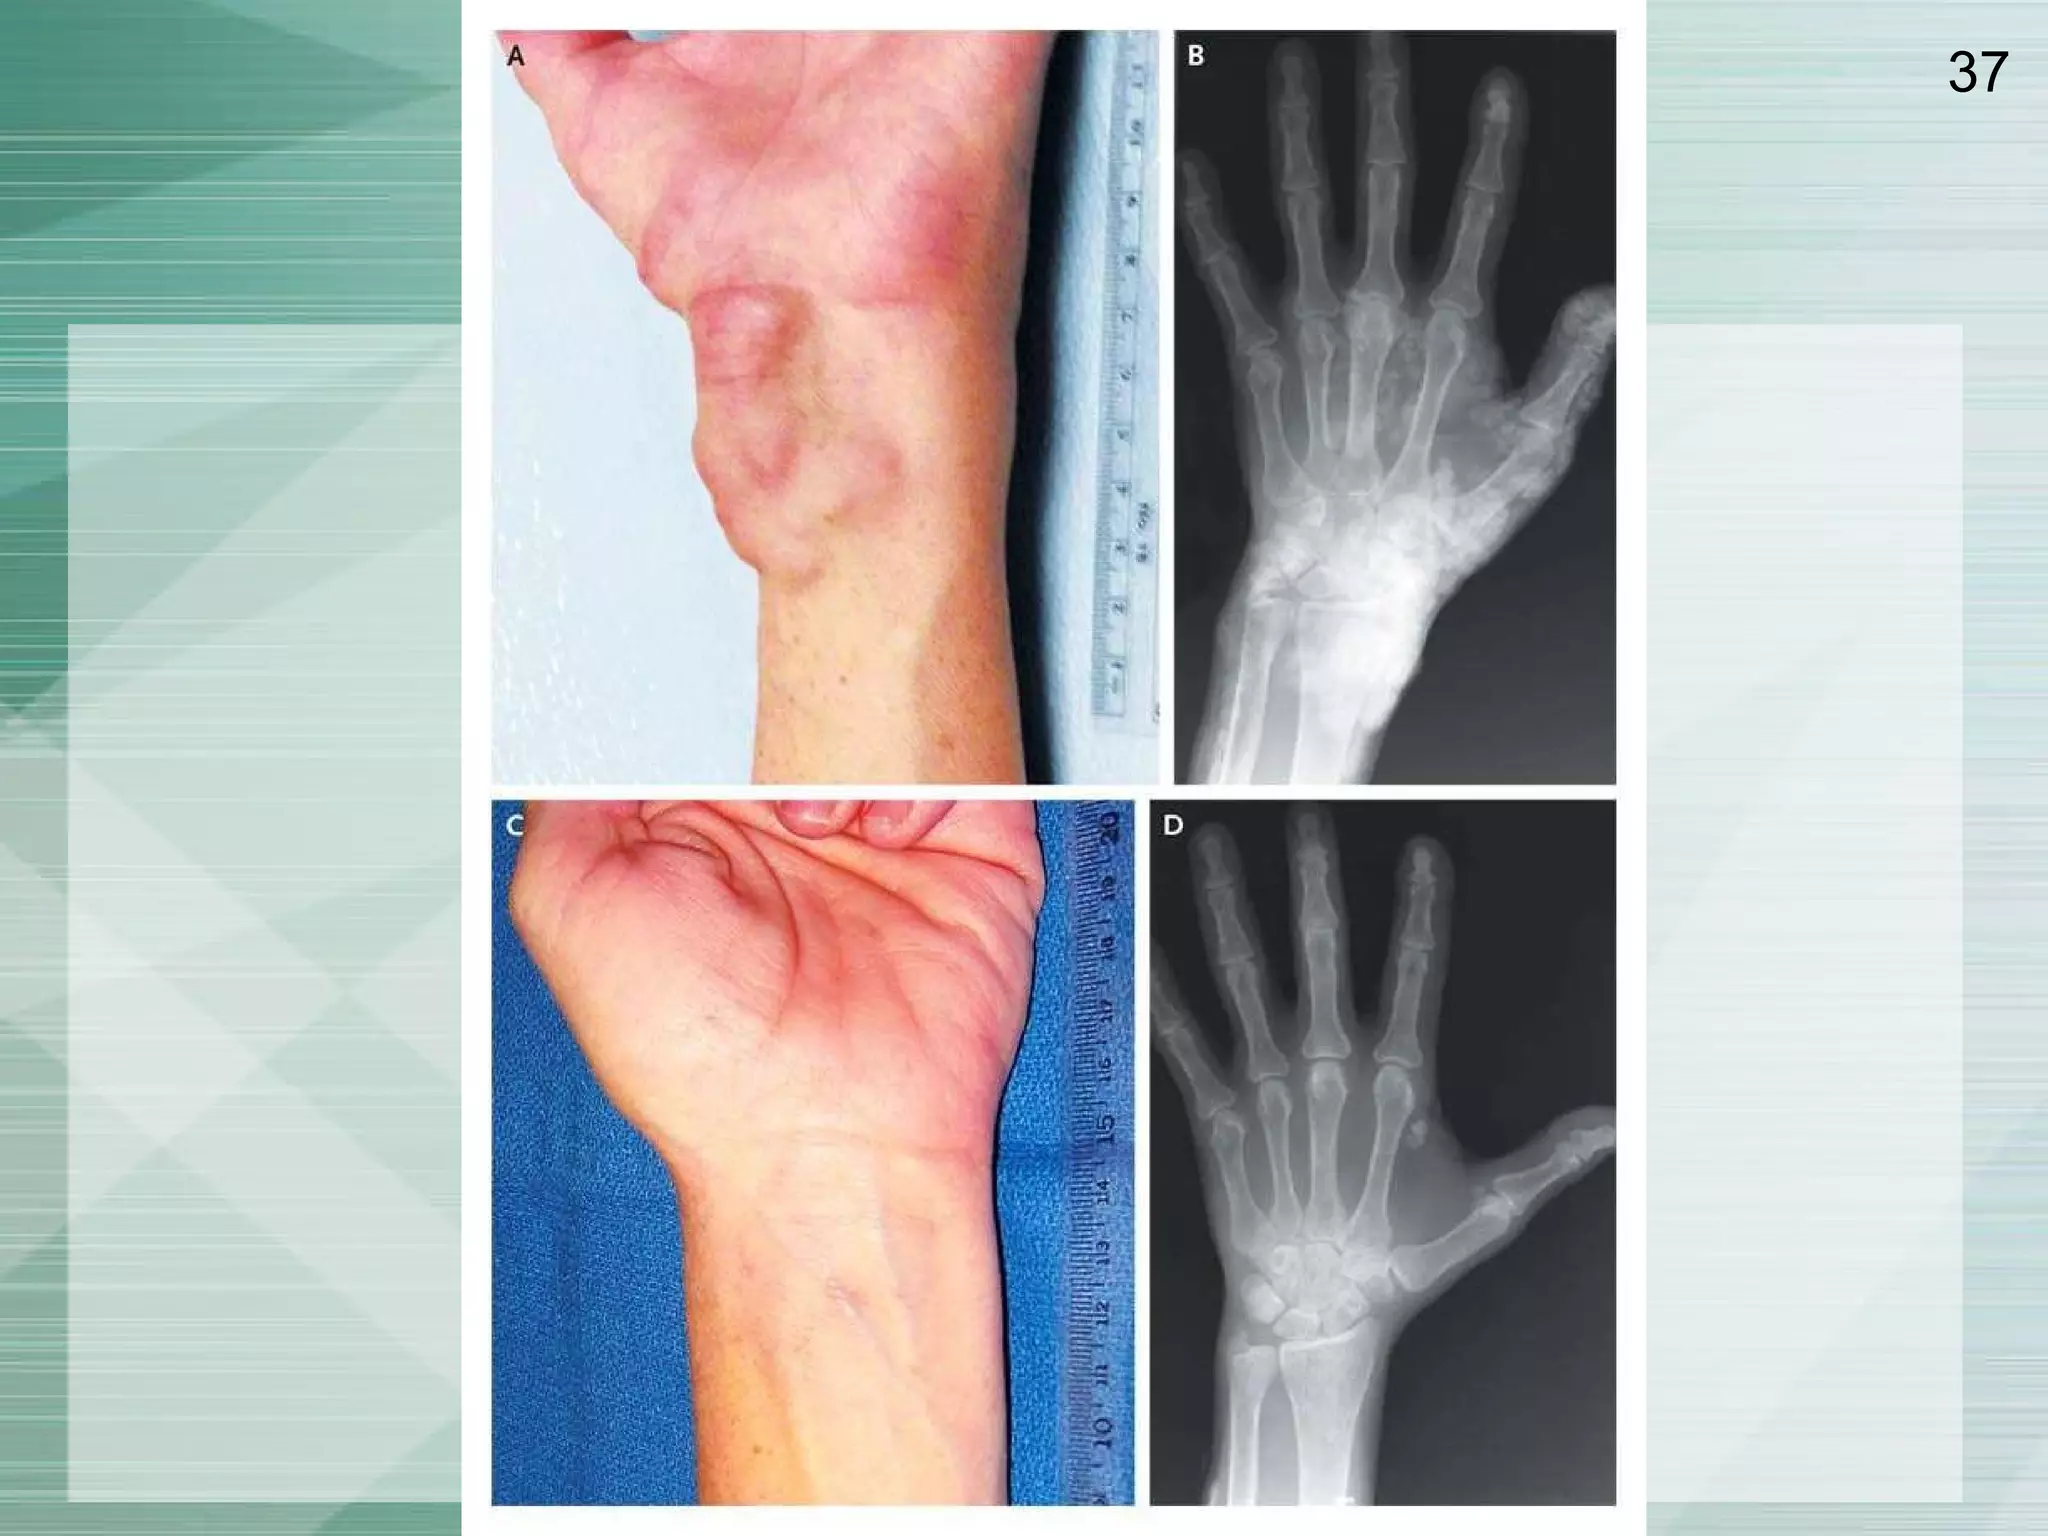

Primary hyperPTH Solitary adenoma 85% Multiple adenoma/hyperplasia 15% MENI : para,pancreas ( ZE synd,gastrinoma,insulinoma, VIPOMA ) ,ant pituitary MENIIa: parathyriod, Medullary,Pheochromocytoma CA 1% Age 60-70 Bone change ( resorption pharygeal tuft,subperiosteal resortion ) FECa>2%

Primary hyperPTH Solitaryadenoma 85% Multiple adenoma/hyperplasia 15% MENI : para,pancreas ( ZE synd,gastrinoma,insulinoma, VIPOMA ) ,ant pituitary MENIIa: parathyriod, Medullary,Pheochromocytoma CA 1% Age 60-70 Bone change ( resorption pharygeal tuft,subperiosteal resortion ) FECa>2%